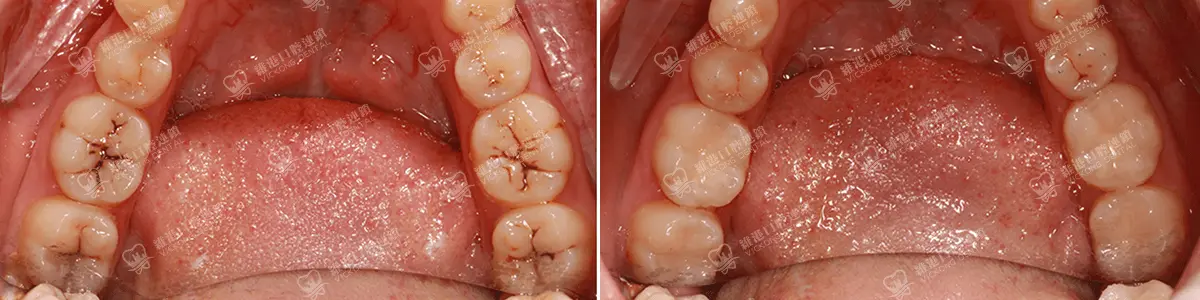

補牙 | 3M p60樹脂補牙

*此資料為維港口腔內部素材,效果因人而異。